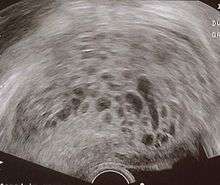

The diagnosis is strongly suggested by ultrasound (sonogram), but definitive diagnosis requires histopathological examination. On ultrasound, the mole resembles a bunch of grapes ("cluster of grapes" or "honeycombed uterus" or "snow-storm"[14]). There is increased trophoblast proliferation and enlarging of the chorionic villi.[15] Angiogenesis in the trophoblasts is impaired as well.[15]